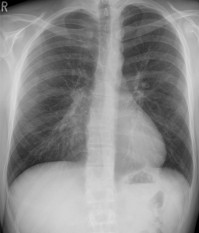

To address the problem of false positives in lung cancer screening Dr. Peikert and Fabien Maldonado, M.D., from Vanderbilt University, along with their collaborators used a radiomics approach to analyze the CT images of all lung cancers diagnosed as part of the National Lung Cancer Screening Trial.

Radiomics is a field of medicine that involves extracting large amounts of quantitative data from medical images and using computer programs to identify disease characteristics that cannot be seen by the naked eye.

Researchers tested a set of 57 variables for volume, nodule density, shape, nodule surface characteristics and texture of the surrounding lung tissue.

They identified eight variables which enabled them to distinguish a benign nodule from a cancerous nodule.